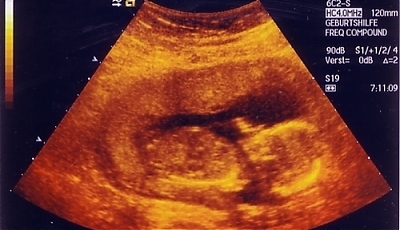

(fot. commons/creative)

Przed takim „wyborem” stanęła Chinka Cao Ruyi, która jest w piątym miesiącu ciąży. Władze Państwa Środka, realizując politykę „jednego dziecka” chcą zabić jej nienarodzoną pociechę. By ochronić swoje dziecko zostało jej jedno wyjście: zapłacić ekstremalnie wysoką karę grzywny.